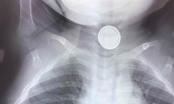

Sáng nay 11-2, tin từ Bệnh viện Đa khoa tỉnh Hà Tĩnh cho biết các bác sĩ Khoa Chẩn đoán hình ảnh vừa nội soi gắp thành công viên thuốc còn nguyên vỉ sắc nhọn trong thực quản cho bệnh nhân Nguyễn Chí L. (65 tuổi, trú tại phường Trấn Phú, TP Hà Tĩnh, tỉnh Hà Tĩnh).

Sau khi thăm khám cho bệnh nhân, các bác sĩ đã tiến hành nội soi gây mê thực quản bằng ống mềm để gắp dị vật. 2 viên thuốc còn nguyên vỉ với các cạnh sắc nhọn, cắm vào thành thực quản của bệnh nhân với đường kính khoảng 2 x 2,5 cm đã được gắp ra thành công.